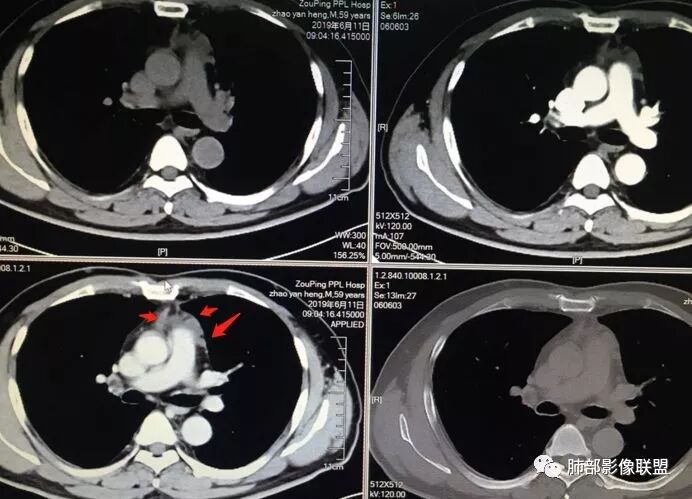

男,59

2015年小,2019年增强,不规则强化不均匀。

48-60-70,28-30-24,不规则渐进性强化,密度不均。

诊断:侵袭性胸腺瘤

标示一下。我们捋一捋征象

边缘张力不高

19 年

根据强化,高的70HU,低的没测,考虑囊实性

实性部分明显强

偏一侧

上面来的血供,病灶深分叶

附近心包似乎也不干净

有淋巴结